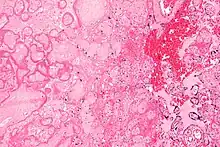

Micrograph of a placental infarct. H&E stain. | |

A placental infarction results from the interruption of blood supply to a part of the placenta, causing its cells to die.

Small placental infarcts, especially at the edge of the placental disc, are considered to be normal at term. Large placental infarcts are associated with vascular abnormalities, e.g. hypertrophic decidual vasculopathy, as seen in hypertension.[1] Very large infarcts lead to placental insufficiency and may result in fetal death.

Maternal floor infarcts are not considered to be true placental infarcts, as they result from deposition of fibrin around the chorionic villi, i.e. perivillous fibrin deposition.